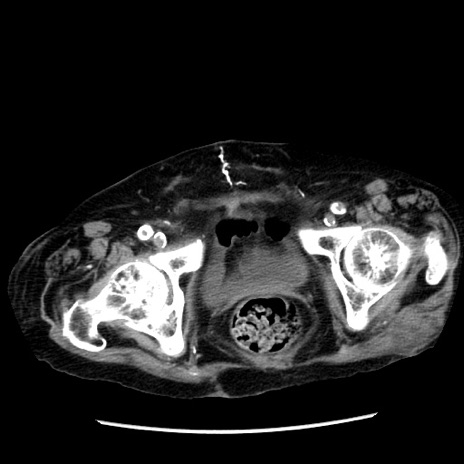

症例14(横断像)

【症例】 90歳代女性

【主訴】 腹痛・嘔吐

【現病歴】今朝から左側腹部痛を認めた。 経過観察していたが、嘔吐を認めたため来院。

【既往歴】 子宮癌術後

【身体所見】 意識清明、BP 127/54mmHg、P 98bpm Sp02 95%(RA)、BT 35.8°C、腹部平坦・軟腸ぜん動音聴取良好、右下腹部圧痛(+) 反跳痛なし

【データ】WBC 9800、CRP 0.46